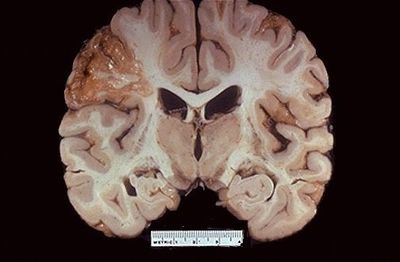

Question

Que patología cutánea se puede visualizar en la imagen

Answer

• Queratosis

• Vesícula

• Nódulo

• Ampolla